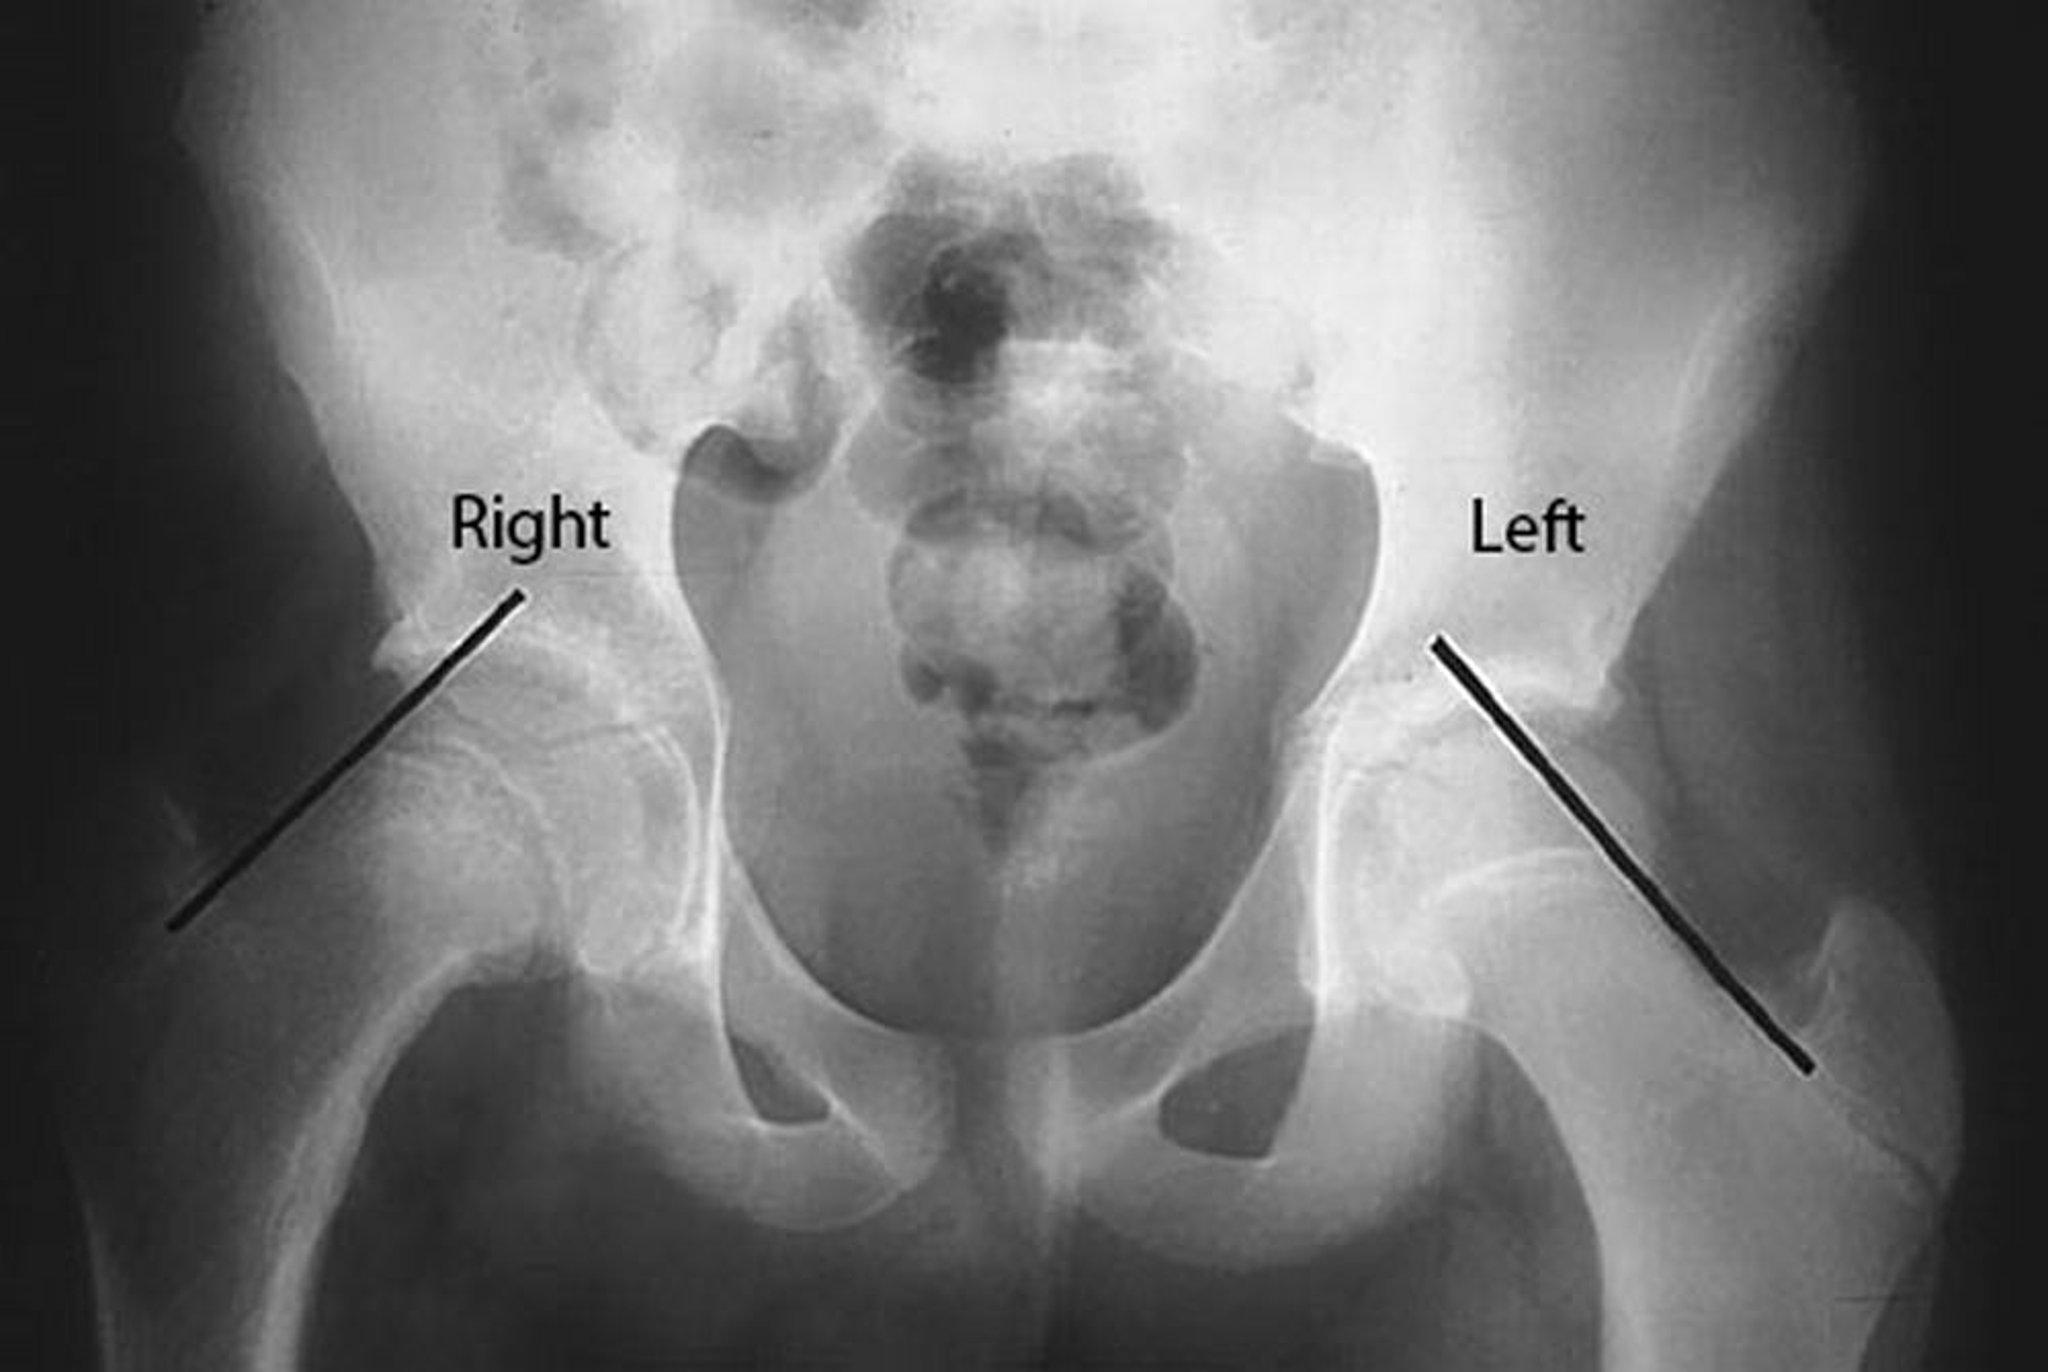

大腿骨頭すべり症(SCFE)

右股関節の大腿骨頭すべり症(SCFE)患者のこのX線写真では,大腿骨頸部上縁にKlein lineを引いてある。患側である右側では大腿骨頭がKlein lineより下にあるのに対し,健側である左側では大腿骨頭の大部分がKlein lineより上にあることに注目すること。